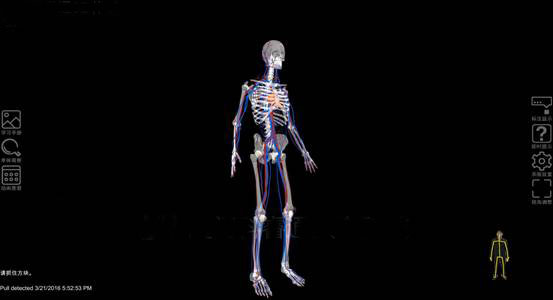

數(shù)字人(rén)體(tǐ)體(tǐ)感互動系統使用(yòng)3D體(tǐ)感攝影(yǐng)機(jī),借助紅(hóng)外(wài)線識别人(ré€n)體(tǐ)的(de)運動,追蹤全身(shēn)動作(zuò),根據掃描數(shù)據,建立數(shù)位骨架&。通(tōng)過大(dà)量的(de)标本影(yǐng)像文(wén)本、圖形、動畫(huà)、聲音(yīn)、視(↓shì)頻(pín)等多(duō)種媒體(tǐ)信息,使抽象、靜(jìng)态、枯燥的(de)理(lǐ)論知(zhī)識變得(de)直觀形象、生(¥shēng)動活潑。使教學由平面走向立體(tǐ),化(huà)抽象為(wèi)具體(tǐ),使學生(shēng)♣在輕松愉悅中接受教育,并激發學生(shēng)的(de)學習(xí)積極性和(hé)主動性,達到(dào)“以學生(shēng)自(zì)學為(wèi)主體(tǐ),教師(shī)指導為(wèi)輔®助”的(de)翻轉課堂的(de)目标。

VR虛拟現(xiàn)實系統主要(yào)由計(jì)算(suàn)機(jī)、輸入輸出設備、虛拟現(xiàn)實設計(jì)/浏覽$軟件(jiàn)等組成。用(yòng)戶以計(jì)算(suàn)機(jī)為(wèi)核心,通(tōng)過輸入輸出設備與應&用(yòng)軟件(jiàn)的(de)虛拟世界進行(xíng)交互。

(1) 科(kē)技(jì)化(huà)、趣味化(huà)相(xiàng)結合的(de)©教學模式 應用(yòng)虛拟現(xiàn)實技(jì)術(shù)來(lái)呈現(xiàn)人(rén)體(tǐ)內(nèi)部組織結構,€同時(shí)引入多(duō)種學習(xí)模式來(lái)激發學生(shēng)的(de)學習(xí)興趣。學生Ω(shēng)可(kě)根據自(zì)己喜愛(ài)的(de)學習(xí)時(shí)間(jiān)、學習(xí)環境。在課前就(jiù)進行(xí★ng)部分(fēn)知(zhī)識點學習(xí),在課堂上(shàng)的(de)實踐學習(xí)中快(kuài)速吸收教學內(nèi)容,并在課後可(kě)針對φ(duì)自(zì)己的(de)薄弱環節再次進行(xíng)實訓學習(xí),以達到(dào)科(kē)技(jì)化(huà)、趣味化(huà)相(xiàng)結合的(de)×學習(xí)目的(de)。